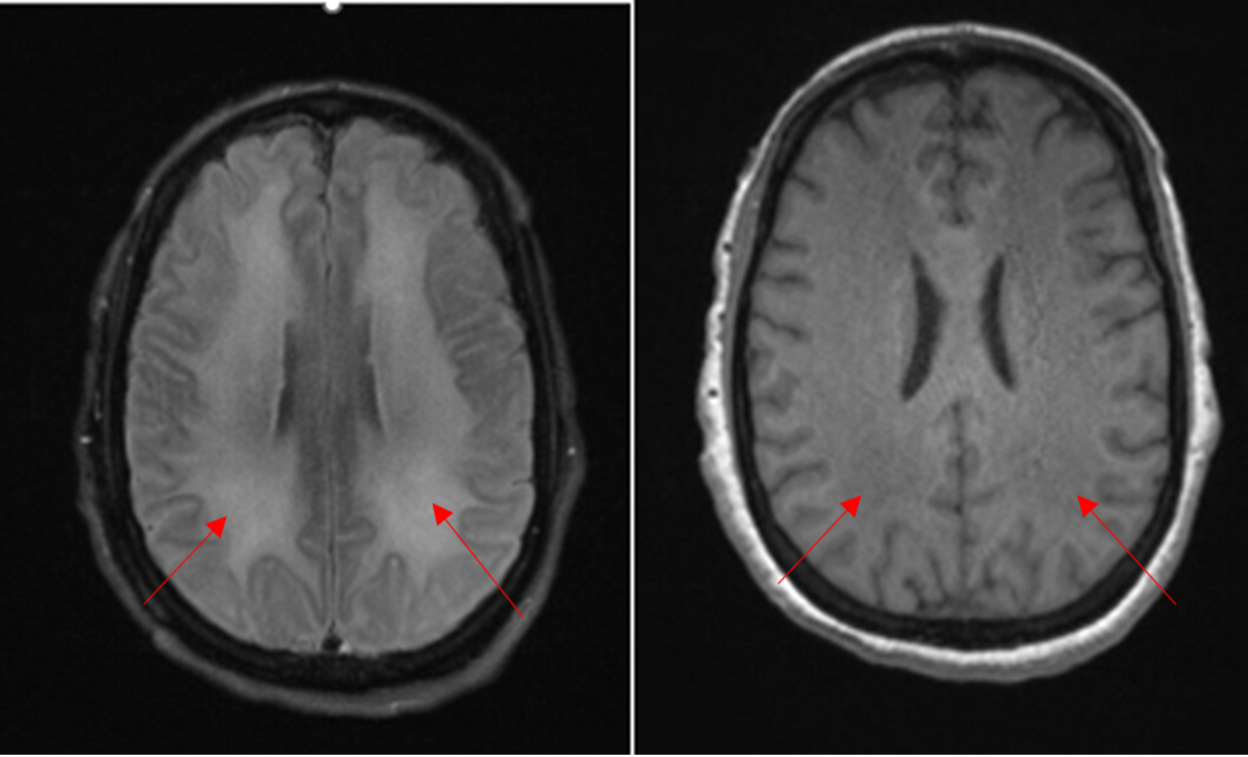

Case Presentation: A 48-year-old woman with history of anxiety, depression, chronic pain, and polysubstance abuse was brought to the hospital for unusual behavior. She was hospitalized one month prior for behavior change and diagnosed with substance induced psychosis. She returned to the hospital after two weeks of recurrent bizarre behavior at home including wandering disrobed, illogical answers to questions, and homicidal ideation. Neurologic exam was non-focal. Select lab data: Urine tox screen positive for cocaine and cannabis. TSH, B12 levels normal. CRP < 0.4 mg/L, ANA negative. CSF: 1 WBC, 0 RBC, prot 37 mg/dL, CSF IgG Index 1:1, encephalopathy panel negative. The initial leading diagnosis was again substance induced psychosis, though we also considered autoimmune encephalitis and metabolic causes. Psychiatry and neurology consulted. The patient’s behavior did not improve over three weeks with trials of anti-psychotics and benzodiazepines. Lumbar puncture revealed oligoclonal bands with an IgG index of 1:1, suggesting intrathecal IgG synthesis, though encephalopathy panel was negative. Subsequent MRI showed signs of diffuse leukodystrophy (Fig 1), raising concern for a toxic or autoimmune process. The imaging results of diffuse leukoencephalopathy in combination with elevated IgG index was consistent with a diagnosis of levamisole-associated multifocal inflammatory encephalopathy (LAMIE) from levamisole-adulterated cocaine use. There were extensive white matter changes seen on MRI, indicating poor overall prognosis. She was given an empiric trial of neuromodulation with IV methylprednisolone for 5 days. Her symptoms were treated with lorazepam, divalproex, and risperidone. While there was modest reduction in her agitation and impulsivity, her condition did not significantly improve and she was discharged to her family’s care.

Discussion: Hospitalists should be familiar with toxic effects of levamisole, a common adulterant of cocaine. While agranulocytosis and cutaneous vasculitis have been well described, a number of recent case reports have described LAMIE. LAMIE is an immune mediated process that causes CNS demyelination, similar in presentation to multiple sclerosis or acute disseminated encephalomyelitis (ADEM). It is characterized by MRI findings with multiple asymmetric white matter lesions, mostly in the periventricular areas. CSF can show pleocytosis, elevated IgG index, or oligoclonal bands, as in our case. A history of cocaine use or positive urine toxicology can distinguish from other etiologies. While there are not clear treatment guidelines, it is treated similarly to other autoimmune disorders with high dose IV steroids. It is also critical that cocaine use, and thus levamisole exposure, is discontinued. While prior case reports have shown favorable prognostic outcomes, our patient unfortunately did not improve. Her prior diagnosis of substance induced psychosis likely delayed her definitive diagnosis of LAMIE and subsequent treatment.